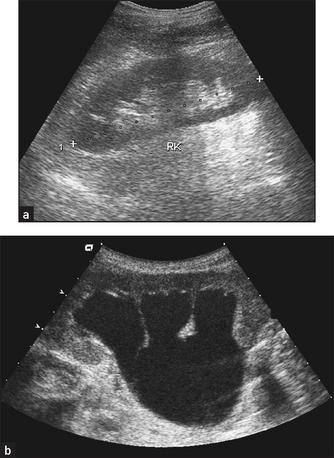

5. Ultrasound to look at renal size and for any renal mass or urinary obstruction (ureters and bladder); and by arterial Doppler to measure renal blood supply. Ultrasound of the scrotum is used to identify scrotal masses. Note the kidneys are usually both small on ultrasound in chronic kidney disease, but the exceptions include diabetes mellitus and amyloid or polycystic kidneys.

Figure 19.4 Ultrasound of (a) normal kidneys and (b) hydronephrosis with cortical atrophy (From Adam A et al. Grainger & Allison’s diagnostic radiology, 5th edn. Churchill Livingstone, 2008.) Churchill Livingstone